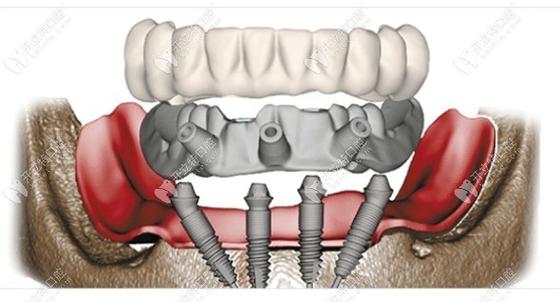

All-on-4种植牙技术作为一种针对半口或全口牙缺失的高效修复方案,通过在颌骨内植入4颗特殊角度的种植体,支撑起整排牙桥,既能快速恢复咀嚼功能,又能避免传统种植中复杂的植骨手术,该技术对患者的条件要求较为严格,需从口腔局部、全身健康状况及个人依从性等多方面综合评估,以确保种植体的长期稳定性和修复效果。

- 骨高度:后牙区种植体需避开上颌窦(上颌)和下牙槽神经管(下颌),通常要求后牙区剩余骨高度≥8-10mm,前牙区≥10-12mm,若骨高度不足,可通过All-on-4特有的倾斜种植体设计(后牙区种植体向远中倾斜45°,避开解剖结构)减少植骨需求,但严重骨缺损(如高度<5mm)仍需结合骨增量手术(如上颌窦提升、骨劈开等)。